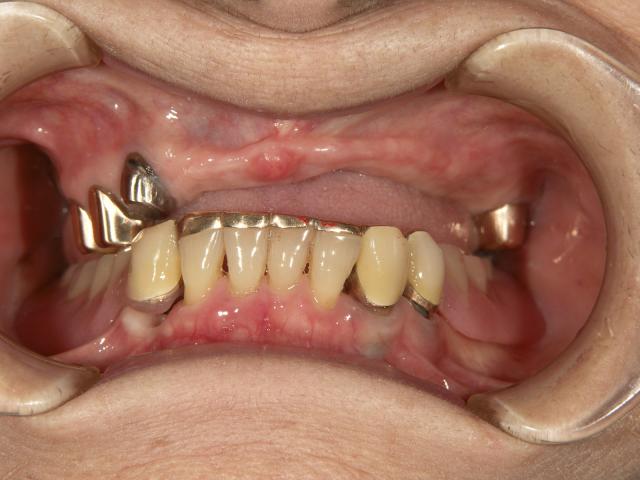

テレスコープタイプの入れ歯(上顎)

2007/04/27

70代女性 担当:院長

義歯が磨り減ってよく噛めない。

唇を噛んでしまう。

前歯の部分が見えないので、自然に見えるようにして欲しい。

術前space術後

術前 術後

1年ほどかけて咬合を挙げてから新義歯作成しました。

新義歯作成 新義歯作成

術後の自然観比較してください!